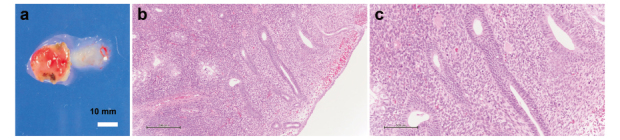

Von Willebrand disease (VWD) is a bleeding disorder caused by a congenital quantitative reduction, deficiency, or qualitative abnormality of the von Willebrand factor (VWF). Here, we report a case of delayed postoperative bleeding in an infertile woman with endometrial polyps complicated by VWD. The patient was a 39-year-old infertile woman with type 2A VWD. At 38 years of age, she was referred to our hospital for infertility and heavy menstrual bleeding. Hysteroscopy revealed a 15-mm polyp lesion in the uterus. The patient was scheduled for transcervical resection (TCR) of the endometrial polyp. Gonadotropin-releasing hormone agonists were preoperatively administered to prevent menstruation. The VWF-containing concentrate was administered for 3 days according to guidelines. The patient was discharged on postoperative day 3 after confirming the absence of uterine bleeding. Uterine bleeding began on postoperative day 6. The patient was readmitted on postoperative day 7 and treated with VWF-containing concentrate for 5 days, after which hemostasis was confirmed. TCR surgery for endometrial lesions is classified as a minor surgery, and guidelines recommend short-term VWF-containing concentrate replacement. However, it should be kept in mind that only short-term VWF-containing concentrate replacement may cause rebleeding postoperatively.